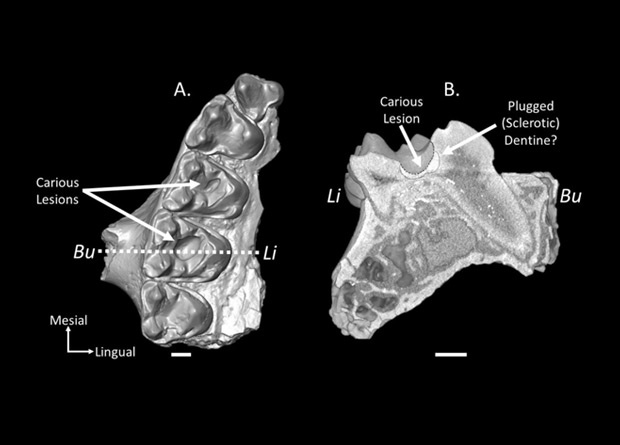

Канадские палеонтологи обнаружили древнейшие следы кариеса у млекопитающих. Проанализировав остатки 1030 примитивных приматов Microsyops latidens возрастом около 54 миллионов лет, исследователи выяснили, что от проблем с зубами страдали 7,48 процента из них. При этом доля особей с кариесом менялась с течением времени. Так, в один из периодов она достигла 17,24 процента, что может указывать на временный переход к диете с большим содержанием фруктов. Как отмечается в статье для журнала Scientific Reports, ранее никто не оценивал распространенность кариеса у представителей ископаемых видов.

Большинство людей хотя бы раз в жизни сталкивались с кариесом зубов. Страдали от него и наши предки. Поскольку основным фактором, повышающим риск кариеса, считается употребление в пищу значительного количества углеводов, у специалистов есть возможность реконструировать рацион древних людей, основываясь на состоянии их зубов. Аналогичная методика подходит и для других видов млекопитающих, в том числе давно исчезнувших. Впрочем, находки ископаемых нечеловеческих зубов со следами кариеса довольно редки и ограничены несколькими вымершими видам медведей, парнокопытных и приматов, включая ранних Homo. Самые ранние из них относятся к среднему миоцену.

Палеонтологи Киган Селиг (Keegan R. Selig) и Мэри Силкокс (Mary T. Silcox) из Торонтского университета решили больше узнать о распространенности кариеса у древних млекопитающих. Они сосредоточили внимание на примитивном примате